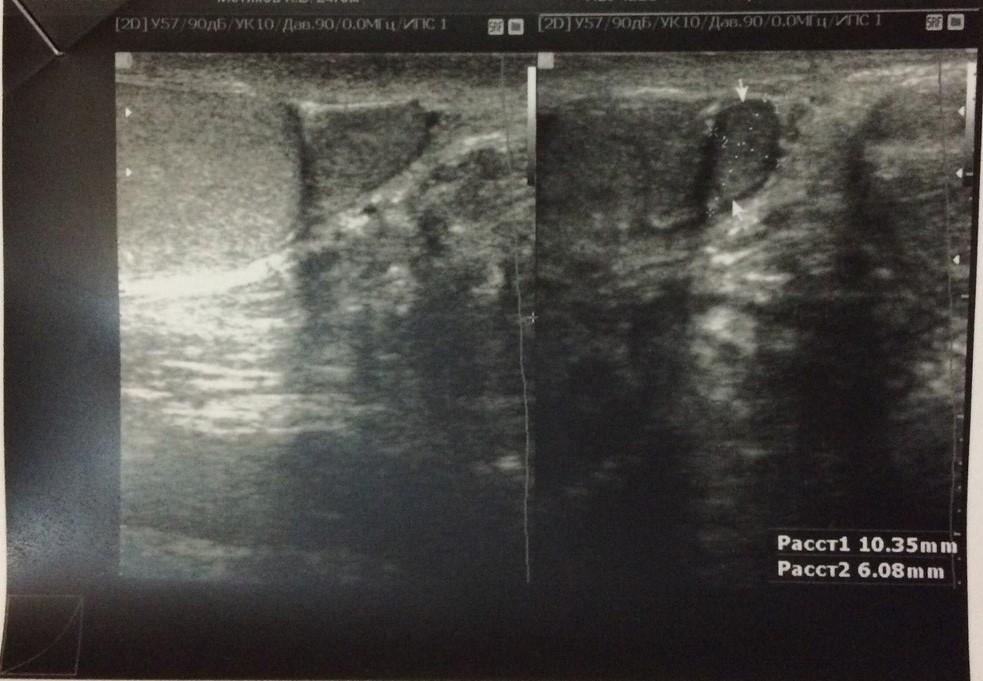

Аденома придатка левого яичка

Около года назад появились сильное боли в придатке левого яичка, при пальпации обнаружил плотное округлое образование, около 1 см. Последние 3 дня участились боли, колит и режет, отдает в левую ногу, боль при ходьбе. Прошел УЗИ. Насколько это опасно? Какой лечение, исход и прогноз ?

Злокачественные образования придатка яичка встречаются крайне редко. То, что описано на УЗИ может быть кистой, заполненной густой семенной жидкостью. Желательно переделать УЗИ в специализированном онкологическом или урологическом учреждении с выполнением допплерографии данного образования, чтобы выяснить его характер (кистозное или мягкотканное) и обратиться на прием к врачу-урологу или онкоурологу. Такие специалисты есть в и интервенционной радиологии им. Н.А. Лопаткина. Вы можете записаться на прием через Call-центр по телефону .